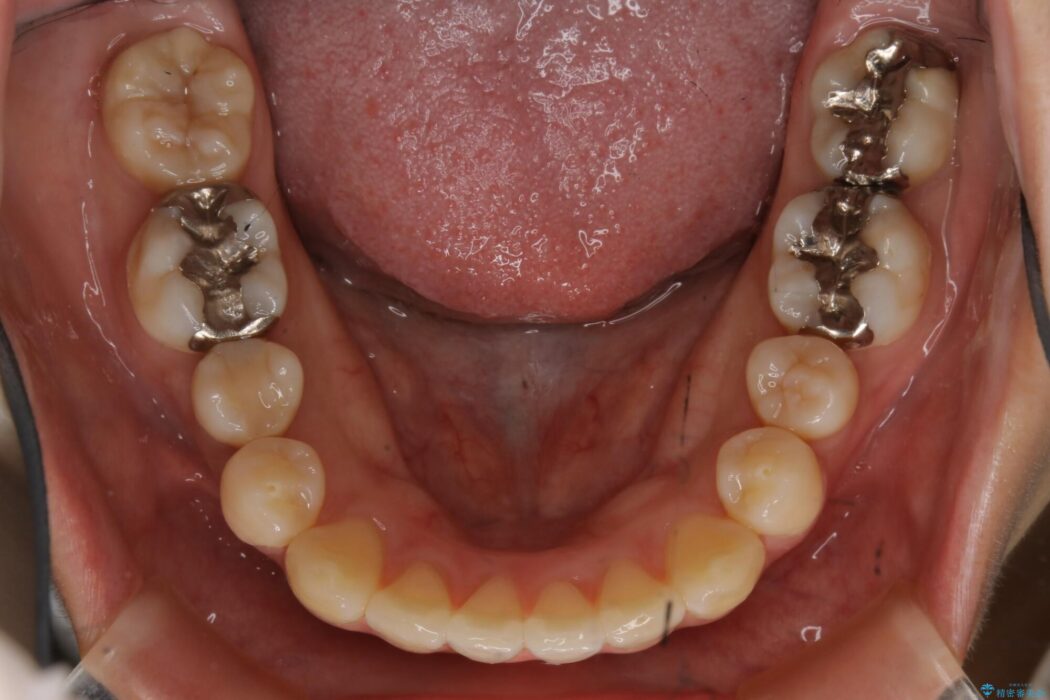

【20代女性】非抜歯でマウスピースの限界に挑戦する矯正治療

前歯を引っ込めるために非抜歯でのマウスピース矯正治療がしたいとの主訴で来院されました。

患者様からなおしたい内容をお聞きしたところ

・上下の歯のガタつき

・出っ歯感(口ゴボ)

・噛み合わせ

よって患者様ご希望の非抜歯かつマウスピースでの矯正を行うために、最大量の臼歯の遠心移動をして歯列全体を奥へ引っ込める計画をご提案しました。